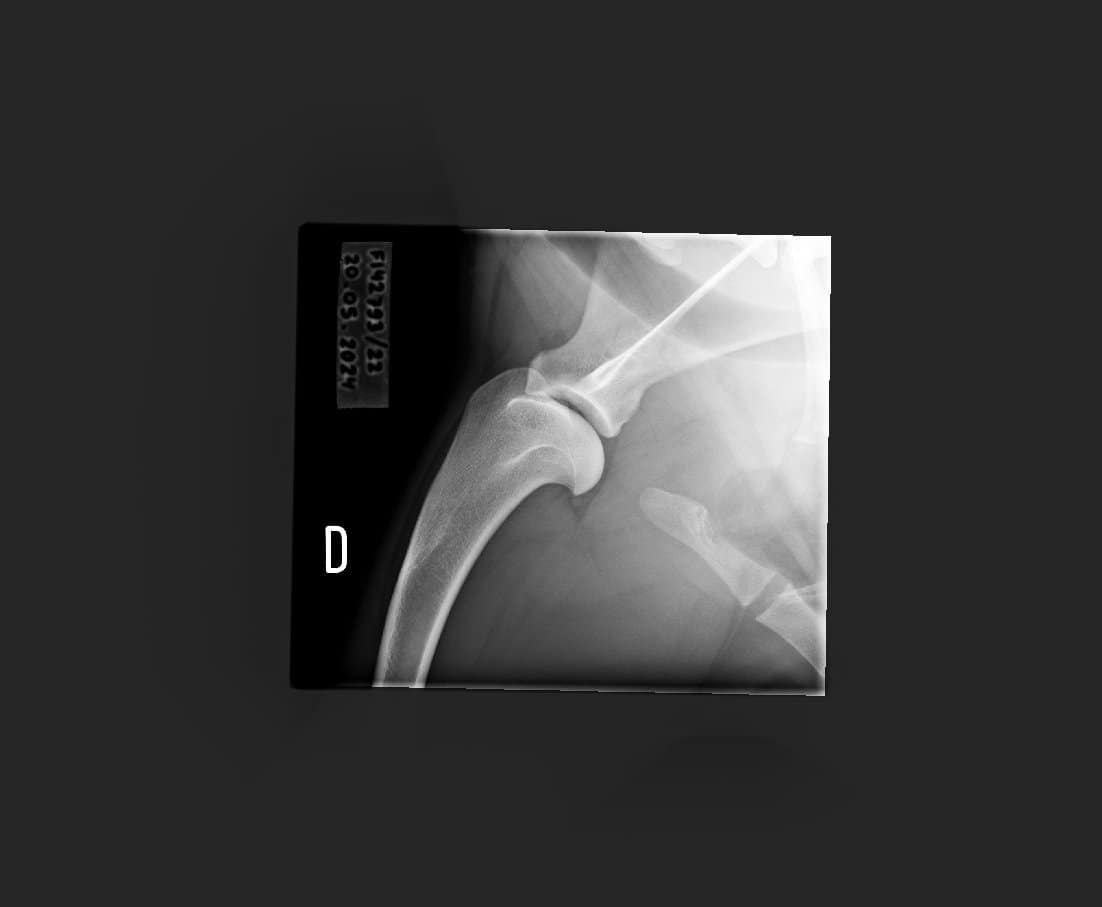

Topin OCD